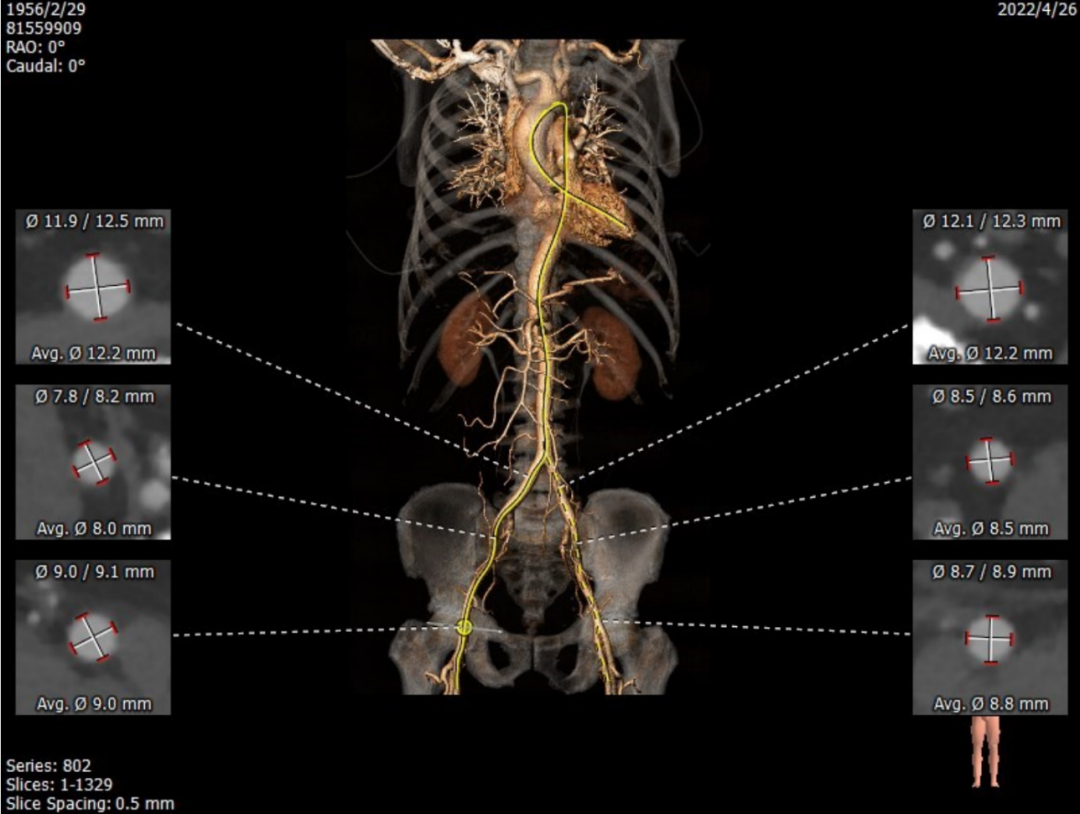

主动脉瓣瓣环周长85.4mm,周长径27.2mm,LVOT 28.1mm,STJ 29.4mm。CT数据分析显示该患者为Type1型二叶瓣,瓣叶重度钙化且增厚,主要分布于无冠瓣叶,左冠窦有团状钙化并延伸至左室流出道,HU850:957mm²。

左冠开口高度13.0mm,右冠开口高度16.5mm,双侧冠脉开口未见明显附壁钙化,结合瓦氏窦宽度和瓣叶长度综合判断冠脉阻挡风险较低。

升主内径36.0mm,主动脉瓣环与水平面夹角39°,主动脉弓角与弓距可。

双侧血管内径可,无明显迂曲和附壁钙化,符合血管入路条件。